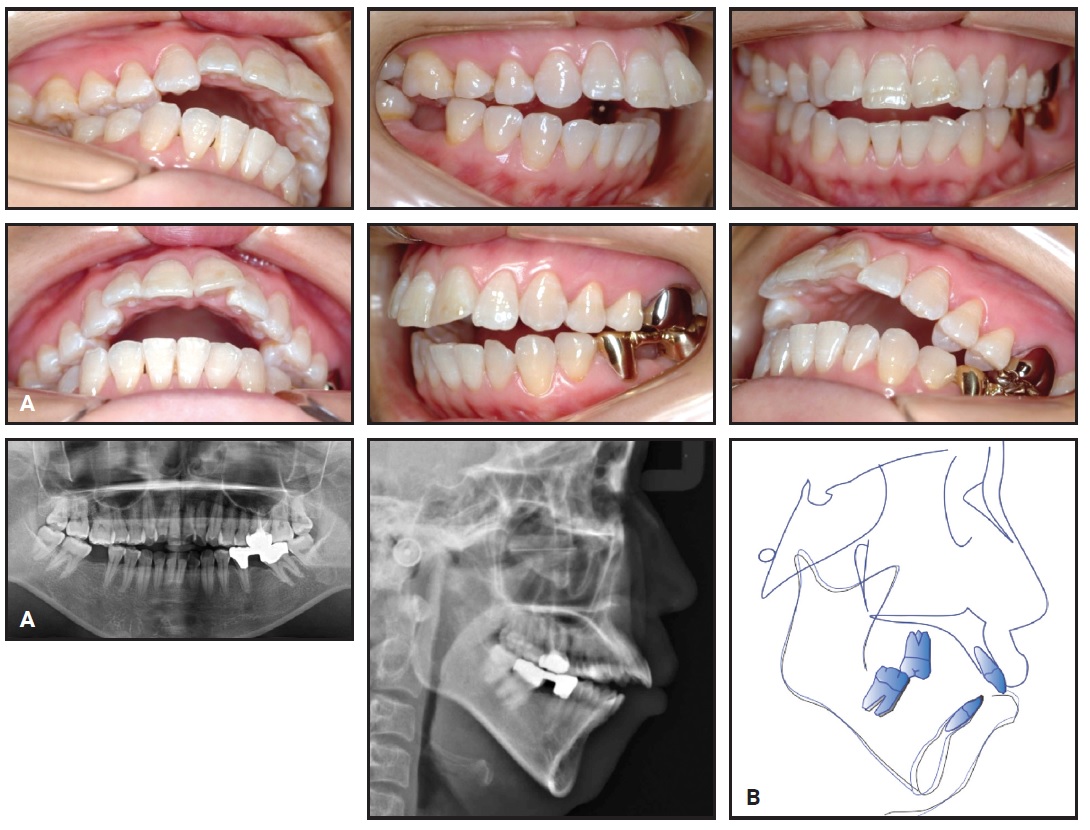

A 25-year-old male presented with the chief complaint of crowding in the mandibular anterior segment, including a complete lack of space for two mandibular incisors (Fig. 1A). He exhibited a balanced facial profile, Class I molar and canine relationships, somewhat narrow maxillary and mandibular arches, crowded upper incisors, and severely crowded lower incisors (Fig. 1B).

Fig. 1 25-year-old male patient with lower anterior crowding, Class I molar and canine relationships, skeletal Class II relationship, and severe overbite and overjet before treatment (continued in next image).

Fig. 1 (cont.) 25-year-old male patient with lower anterior crowding, Class I molar and canine relationships, skeletal Class II relationship, and severe overbite and overjet before treatment.

Cephalometric analysis indicated a Class II skeletal relationship with a slightly protrusive maxilla and a slightly retrusive mandible (Table 1). The overjet and overbite were extreme because of the lower crowding. The maxillary incisors were vertically inclined and slightly retrusive, while the mandibular incisors were labially inclined and protrusive. The nasolabial angle was within the normal range. A panoramic radiograph confirmed the absence of the third molars, which had been extracted previously.